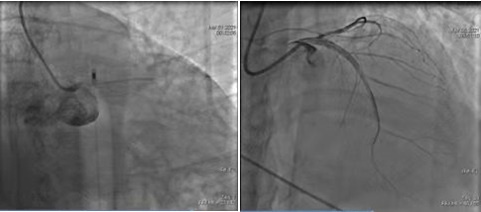

2016年我院开始筹备胸痛中心建设,经过不断探索及改进,于2017年4月成功通过国家胸痛中心认证,成为省内第三家、咸阳市首家通过国家标准版胸痛中心。我院胸痛中心建设5年来,牢记“时间就是生命、时间就是心肌”,规范持续优化急性胸痛救治流程,严格执行时间管理,救治胸痛患者近万例,平均D-W时间缩短至60min以内,最短D-W时间17分钟。延安大学咸阳医院急性胸痛(心肌梗塞、主动脉夹层动脉、肺栓塞等)救治在省内处于领先地位,带动、促进咸阳市急性胸痛救治水平的发展。

经过5年的完善和提升,延安大学咸阳医院胸痛中心各项指标达到国内先进水平,成为省内首批通过国家胸痛中心再认证的单位,是对我院胸痛中心在技术力量、质量标准、救治能力等的再次肯定。延安大学咸阳医院心血管病院年完成介入诊疗10000台次以上,冠脉介入治疗3000例次以上,专用介入手术室3间,配备有血管内超声(IVUS)、冠脉内光学相干成像(OCT)、FFR、RFR等精准化治疗设备,极大的改善了冠脉介入治疗的远期预后。此次获得国家胸痛中心再认证授牌,将促进延安大学咸阳医院胸痛救治、介入诊疗技术水平的进一步提高,更好的为广大人民服务,助力健康中国梦!